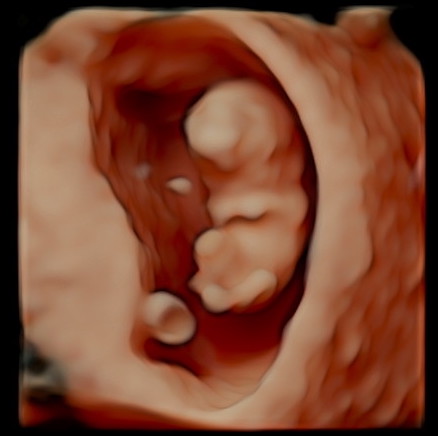

RealBaby™ Scan

Ireland's first RealBaby™ images - Turning 3D into RealBaby™ images for timeless keepsakes and a first true look at your baby.

Our state-of-the-art facility offers cutting-edge ultrasound technology, including Ireland's first RealBaby™ imaging service, ensuring that every detail is captured with unparalleled clarity.